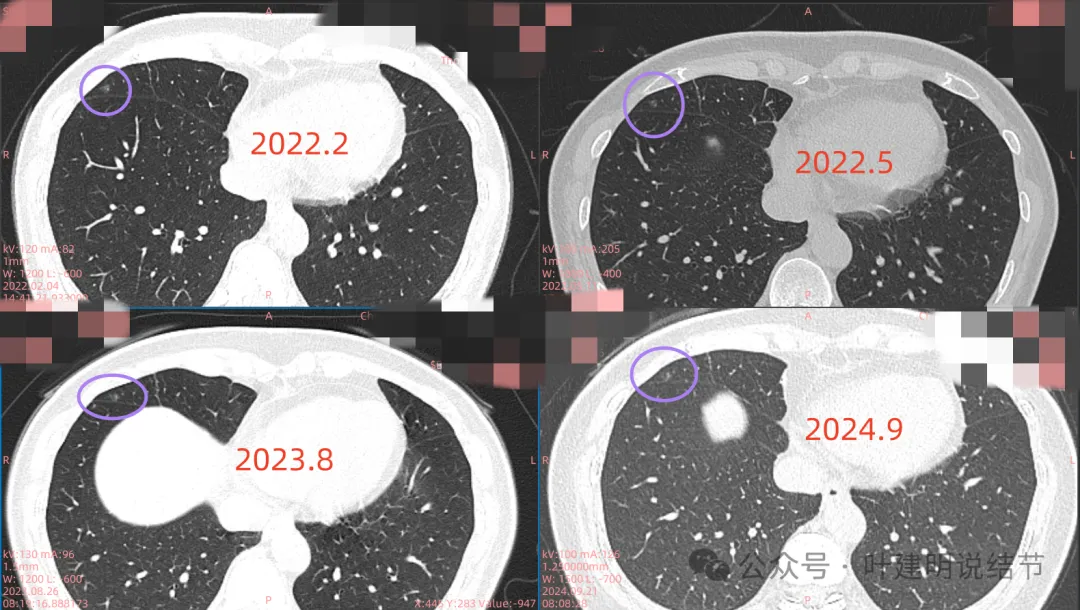

右中叶病灶也是淡的磨玻璃密度,瘤肺边界稍显不清,密度不是太均匀。大概是肺泡上皮增生或不典型增生之类的可能性,也可能慢性炎伴少许纤维增生。

左上叶磨玻璃结节,有微小血管进入,整体轮廓较清,瘤肺边界不如右上主病灶清楚,但持续存在的话,基本上也是肿瘤范畴的。

再看2022年5月时的影像:

这时B医院医生主张手术时的情况:

三处病灶均仍在,间隔3个月显然说不上明显进展或变化。这时候问诊我,我对比后认为风险仍低,能再随访,结友停掉了本已经预约的手术。

再看2023年8月时复查的影像:

有变化吗?说不上!

最后来看2024年9月,也就是叫停手术后2整年之后复查的情况:

仍说不上有明显进展,如果将这几次的放在一起来对照,就会更加直观:

病灶基本上没有明显变化。当然不必过于在意具体大小有没有几毫米的差别,也不必在意具体CT值有几十或百把的区别,微细的差别不影响临床决策,也就是说改变都不足以让肉眼发现的,怎么会影响预后呢!

我看了你2022年2月时的片子,以及某医院建议你手术说有进展时的2022年5月时的片子和2023年8月复查时的片子,再对比2024年9月时的影像,总体上明显点的病灶仍是这三处。首先均仍是纯磨,有的似有微血管进入或穿行,但磨玻璃成分密度很淡,而且大小无明显进展。至于右上病灶是否有缩小好转,感觉上右上的与右中叶的都略显淡了点,我怀疑还是扫描条件不一的关系,本身又是非常小而淡的病灶,可比性稍差,并不能说明必是有吸收好转。但肯定说不上有进展,风险仍是低的,半年或一年复查随访(个人倾向可以年度复查)总归不至于会耽误病情。意见供参考!